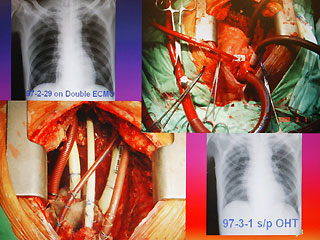

病人陳先生感染細菌性心內膜炎,造成心臟破壞(左下方),進行全心臟摘除術,并放置葉克膜(右上方)體外維生系統以維持生命。

報道說,現年60歲的陳先生,2月初因發現感染細菌性心內膜炎,致使整顆心臟感染嚴重,從奇美醫院轉到臺大醫院之后,經家屬同意,決定進行全心臟摘除,然后置入葉克膜維持生命。陳先生最后靠著葉克膜撐過16天,奇跡式活下來,于今天順利出院。

臺大醫院心臟血管外科教授王水深率領團隊執行這個艱難的手術。他說,陳先生心臟的三尖瓣膜等處已被細菌噬光,無法修補,最后“走投無路”之下,決定先摘除心臟,而家屬的決定也需要相當大的勇氣。

王水深說,摘除心臟時沒人能保證有心臟可換,而靠葉克膜體外維生系統通常也只能維持7天左右,但陳先生靠著兩套葉克膜奇跡式的撐過16天,克服感染及排斥,又能幸運的等到心臟捐贈者,他強調,翻遍文獻可說史無前例。(周先)